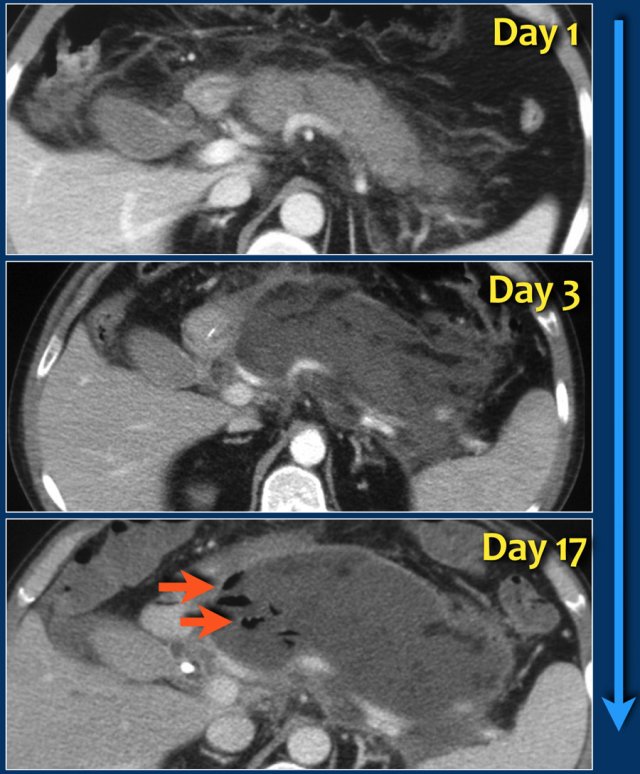

This case is a typical example of infected pancreatic necrosis.

- On day 1 there is enhancement of the pancreas and it just looks like a mild interstitial pancreatitis.

- On day 3 there is no enhancement of the pancreas, consistent with necrosis.

The necrosis also involves the peripancreatic tissue.

So this is an ANC - acute necrotic collection. - On day 17 there are gas bubbles in the necrotic collection consistent with infected pancreatic and peripancreatic necrosis.

A wall surrounds the collection.

The term pancreatic abcess is no longer used, since a collection of pus without necrotic tissue is extremely uncommon in acute pancreatitis.